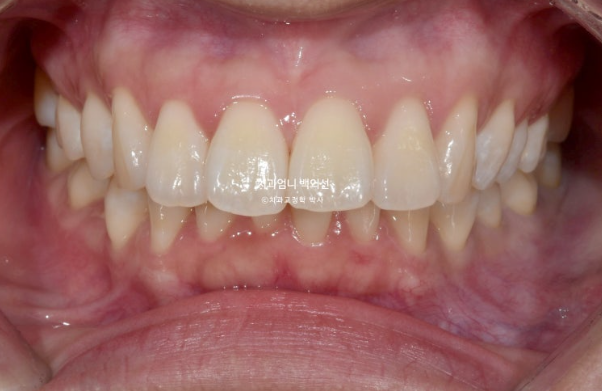

정면을 보시면 윗니가 아랫니를 많이 덮고 있습니다.

아랫니가 거의 보이지 않습니다.

이런 부정교합을 과개교합 이라고 합니다.

윗니도 많이 뻗쳐 있습니다.

배열도 좋지 않아서 발치교정 권유드렸습니다.

개선된 과개교합과 일치된 중심선

앞니 뻗침도 많이 좋아졌습니다.